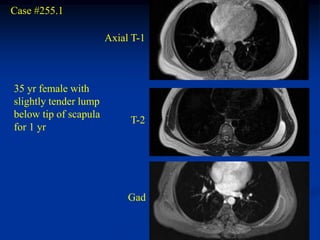

Case #255.1

Axial T-1

35 yr female with

slightly tender lump

below tip of scapula

T-2

for 1 yr

Gad